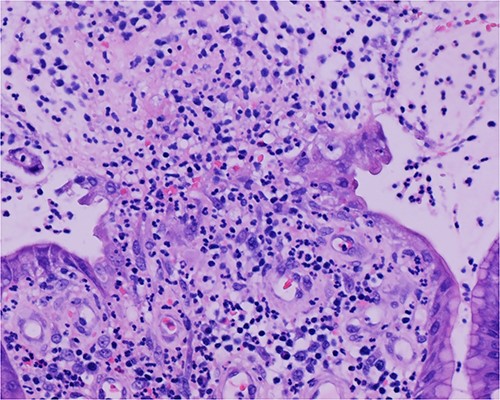

Histologic sections of the polyps demonstrated benign gastric hyperplastic polyps with acute and chronic gastritis (Fig. 2). Portions of the gastric polyps and adjacent mucosa were covered by inflammatory cell exudate (Fig. 3). Higher magnification revealed conspicuous volcanic-like eruption of the exudate, reminiscent of pseudomembranous gastritis (Fig. 4). Alcian yellow and GMS stains were negative for Helicobacter pylori and fungal organisms, respectively.

Volcanic-like eruption of inflammatory exudate, reminiscent of pseudomembranous gastritis.